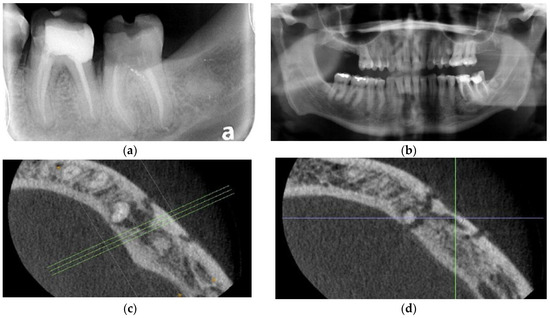

3.1. Case 1

3.2. Case 2

3.3. Case 3

3.4. Case 4

3.5. Case 5